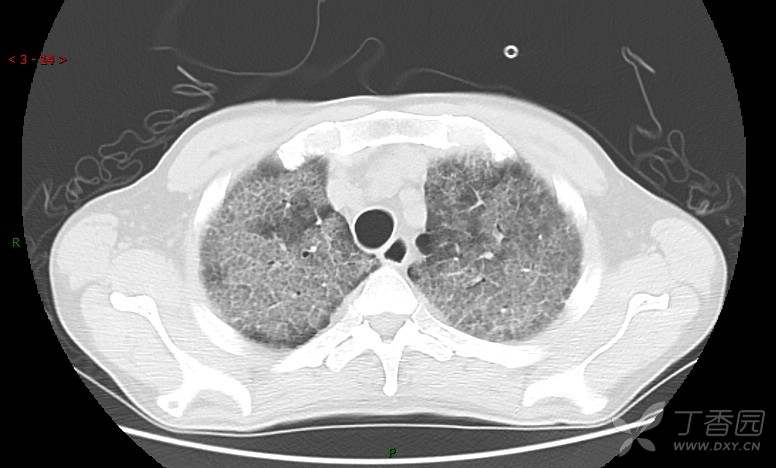

地图+铺路石征=PAP?那升高的CEA怎么说(病例3连发,附其他2例链接)

患者男,42岁,咳嗽半年余,加重伴憋喘2月余。

患者半年余前无明显诱因出现间断咳嗽,干咳为主,偶咳少量黄白痰,剧烈咳嗽或运动后可出现轻度憋喘,无高热、脓臭痰,无胸痛、咯血及晕厥,无低热乏力及盗汗,无心前区压榨感及夜间阵发性呼吸困难,初未在意,未予正规诊治。2月余前患者自觉上述症状较前加重,咳嗽、憋喘明显,黄白色粘痰略有增多,伴有发热,热前伴有畏寒、寒战,体温最高达38.9℃,先后就诊多家医院,入住重症监护室,未行气管插管,考虑“重症肺炎”,给予“美罗培南、复方磺胺甲噁唑”等药物抗感染,“卡泊芬净”抗真菌,并给予“甲泼尼龙”等药物治疗35天,经治疗后症状好转于2018-04-02出院。患者自出院后仅应用中药治疗(具体不详),并给予家庭氧疗,平素仍有间断咳嗽,咳少量黄白色粘痰,活动后憋喘明显,活动耐量差,以卧床为主。

肺内弥漫性网状结节影,PET-CT却无阳性病灶,这是?(附其他2例链接)